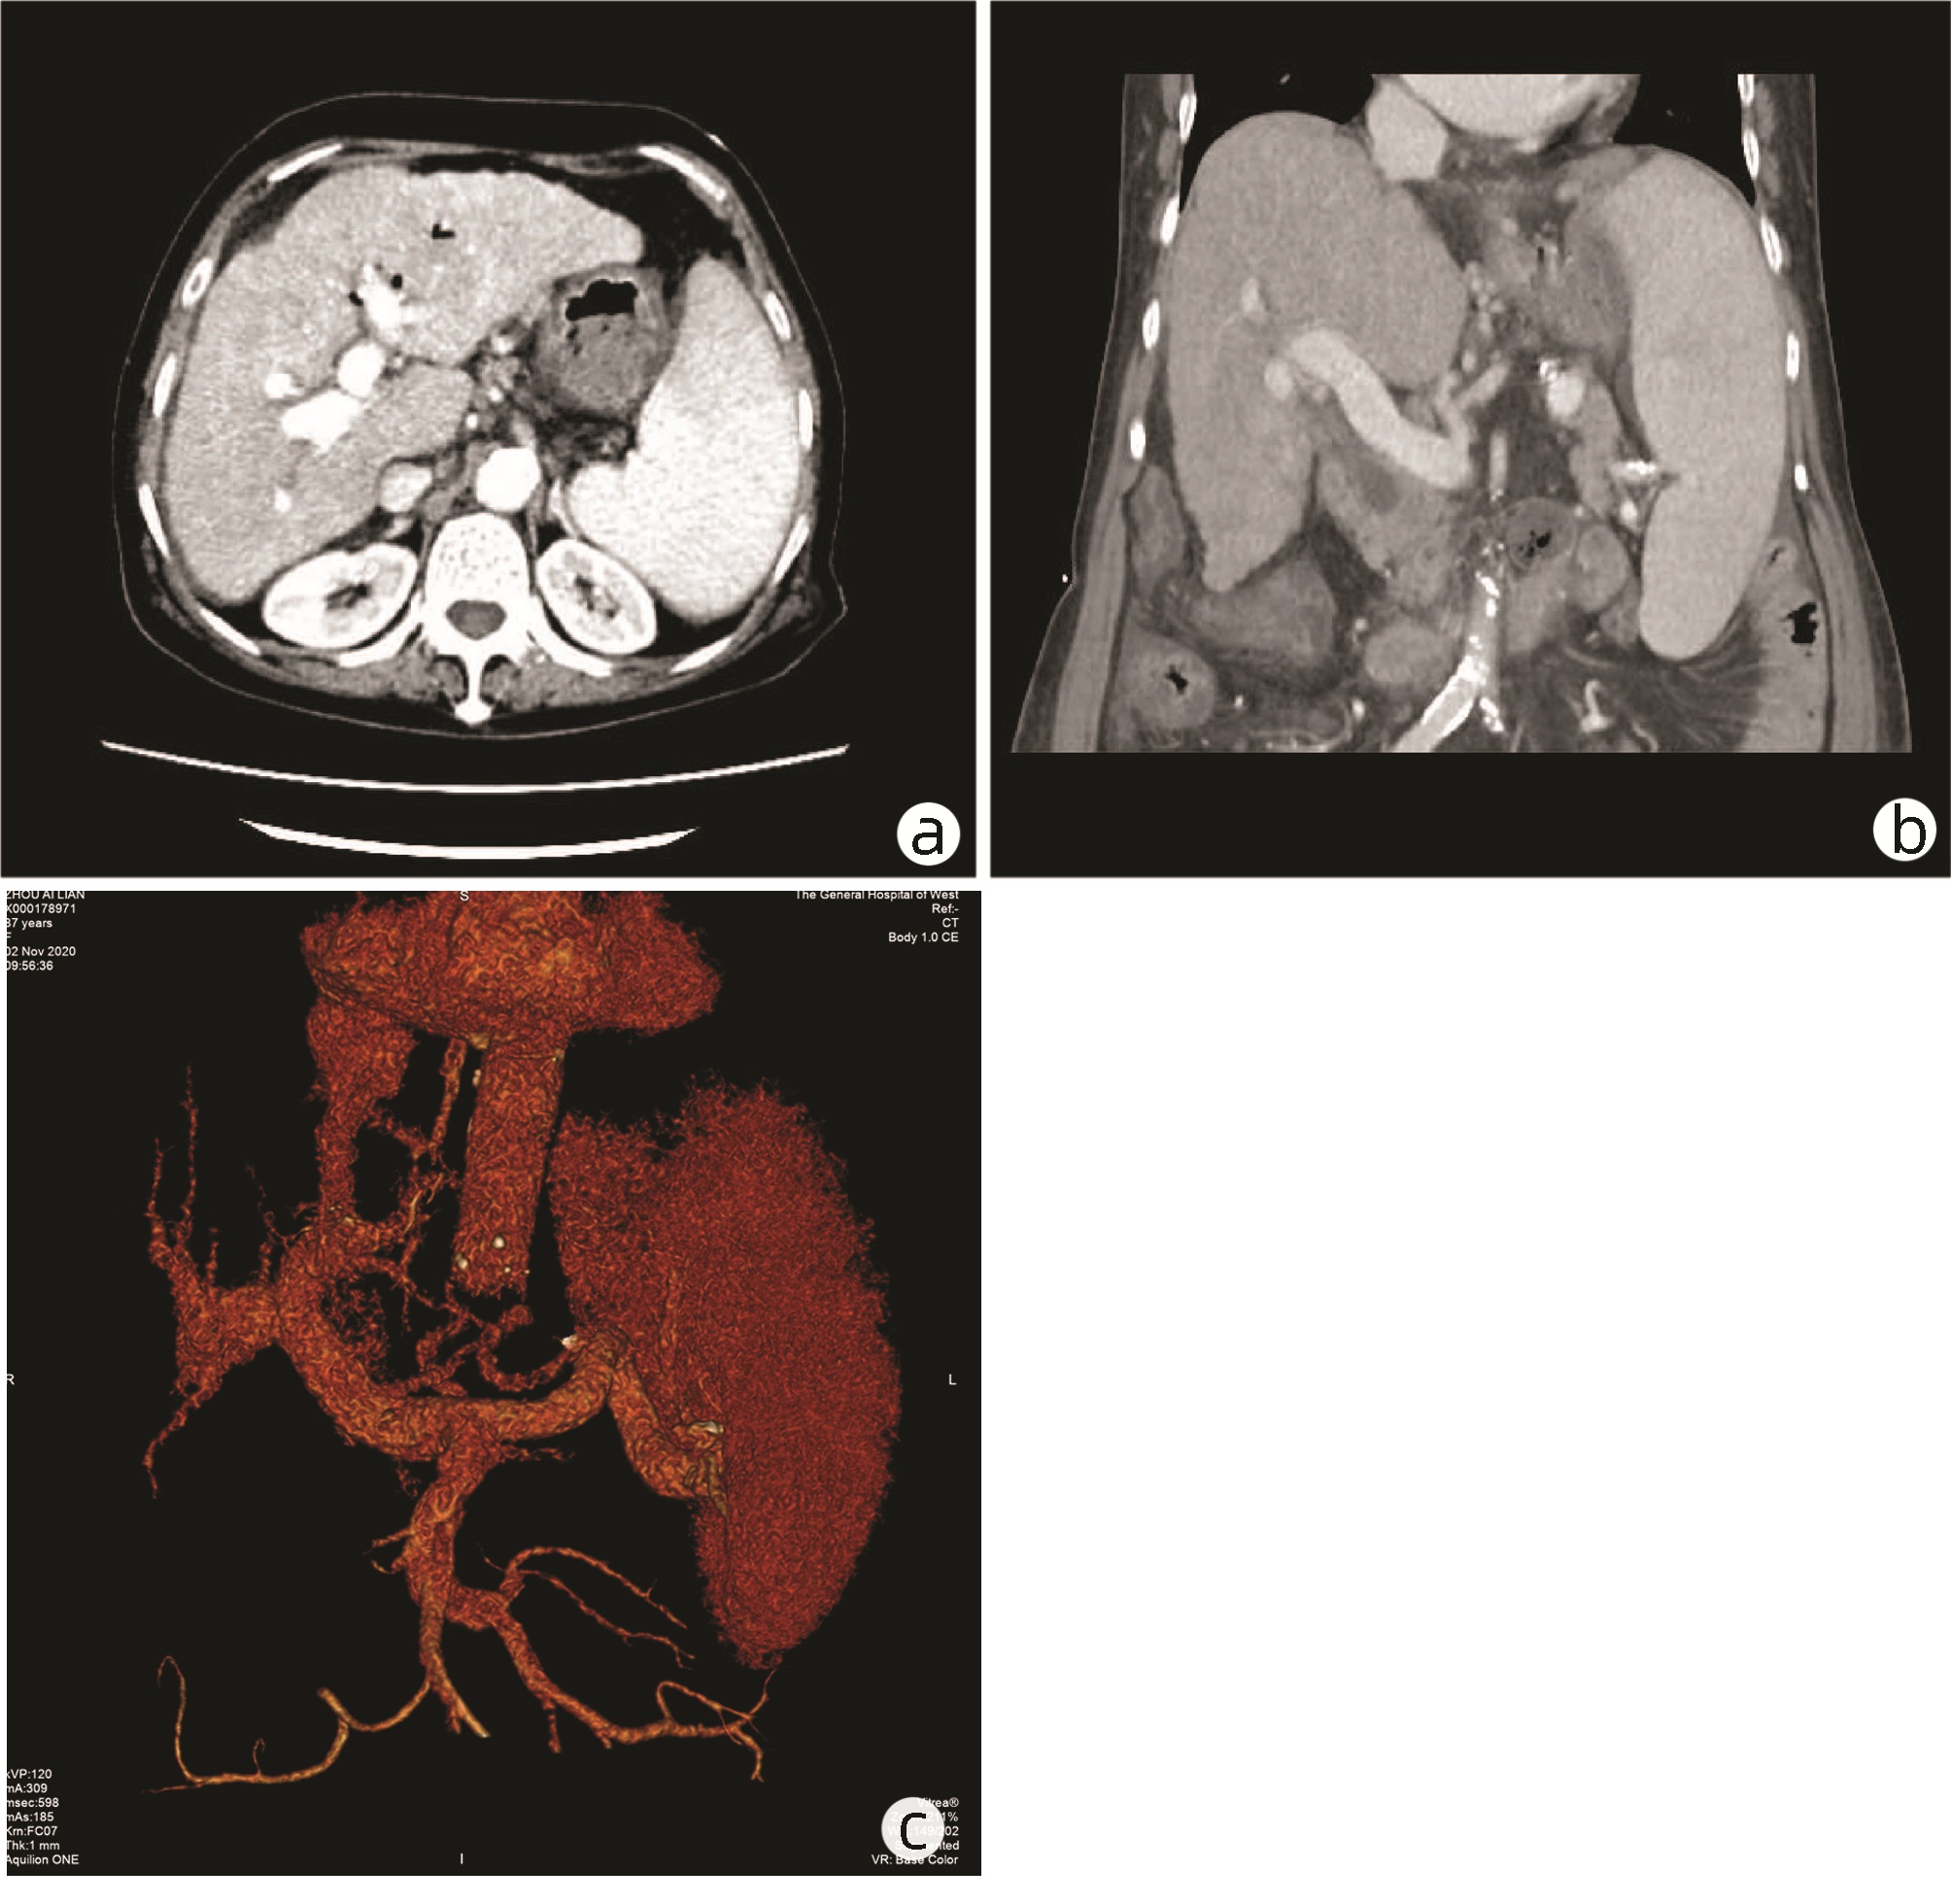

可切除胰腺癌术前评分分级体系的建立与应用

王成方, 王之江, 王伟林

2022, 38(10): 2325-2333. DOI: 10.3969/j.issn.1001-5256.2022.10.023

摘要(1021) HTML (589) PDF (2058KB)(81)

摘要:

目的  探讨分析可切除胰腺癌早期复发的危险因素及评分分级体系的建立与应用。  方法  采用回顾性病例对照研究方法,纳入浙江大学医学院附属第二医院肝胆胰外科2015年3月—2021年6月行根治性切除手术的可切除胰腺癌患者303例,其中283例直接手术患者分为早期复发组(术后6个月内)(n=95)和非早期复发组(n=188);术前行新辅助治疗患者20例为新辅助治疗组。观察指标包括患者的一般资料及术前影像资料;患者术前实验室检验资料,血常规、血生化及衍生指标,肿瘤标志物及凝血指标;随访获得无复发生存情况。正态分布的计量资料两组间比较采用t检验;非正态分布的计量资料两组间比较采用Mann-Whitney U检验。计数资料两组间比较采用χ2检验。通过受试者工作特征曲线确定各指标的最佳临界值。采用多因素Logistic回归分析胰腺癌患者早期复发的危险因素。绘制Kaplan-Meier曲线并采用Log-rank检验比较各组患者的无复发生存期。  结果  单因素分析结果显示,与非早期复发组相比,早期复发组患者BMI、甘油三酯较低,CA19-9、CA242、CA125、血浆纤维蛋白原较高(P值均<0.05)。多因素Logistic回归分析结果显示,BMI(OR=1.150,95%CI:1.038~1.273,P=0.007)、血浆纤维蛋白原(OR=2.513,95%CI:1.355~4.663,P=0.003)和CA242(OR=2.482,95%CI:1.067~5.774,P=0.035)是可切除胰腺癌患者早期复发的独立危险因素。将BMI、CA242、血浆纤维蛋白原3项指标纳入评分分级体系,临界值分别为23.00 kg/m2、30.00 U/mL和4.00 g/L。BMI<23.00 kg/m2计为1分,否则计为0分;CA242≥30.0 U/mL计为1分,否则0分;血浆纤维蛋白原≥4.00 g/L计为1分,否则0分,总分为0~3分。对早期复发与非早期复发患者进行评分,结果显示早期复发组评分更高[2(0~3)分vs 1(0~3)分,Z=-5.339,P<0.001]。Kaplan-Meier曲线分析结果显示,不同评分组别的患者无复发生存时间比较差异有统计学意义(χ2=28.116,P<0.001),分值越高预期无复发生存时间越短。将3分定义为高危组,0~2分定义为低危组。高危组早期复发率为84.6%,低危组早期复发率为31.2%。  结论  基于BMI、血浆纤维蛋白原和CA242这3项指标建立的评分系统能够在一定程度上预测患者术后复发情况。